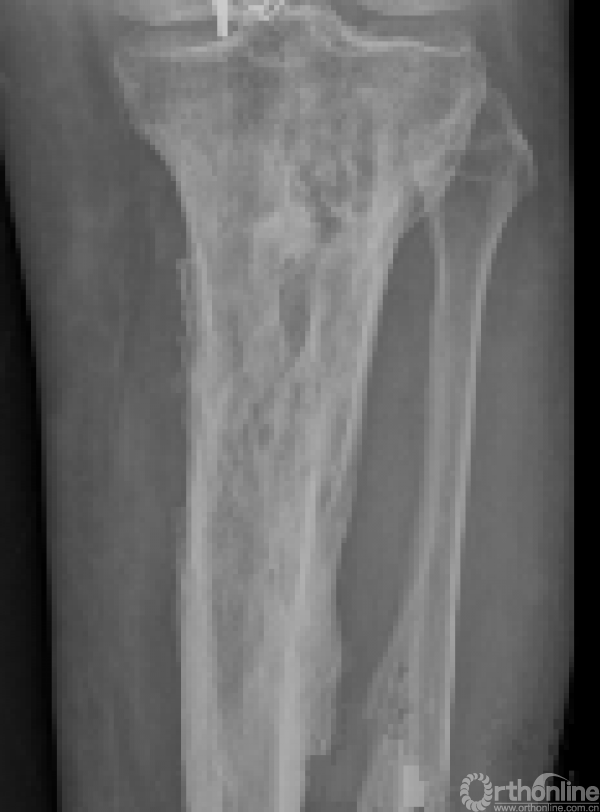

临床上常见反复发作,严重影响身心健康和劳动能力。急性骨髓炎起病时高热、局部疼痛,转为慢性骨髓炎时会有溃破、窦道形成、流脓、有死骨或空洞形成。重症患者可能会危及生命,有的不得不采取截肢的办法,致患者终生残疾。影像学和病理表现如下图。